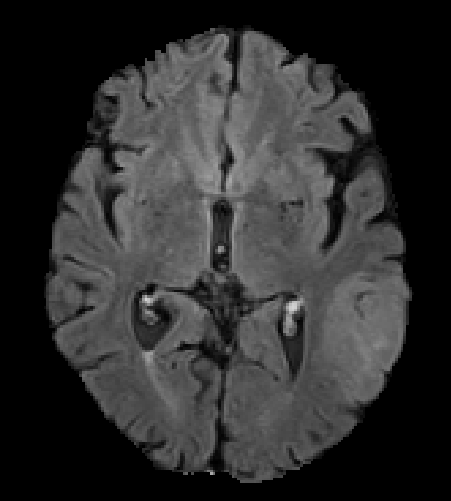

The proposed model outperforms some of the ensemble approaches which is shown in Table 4. Fig. 2 shows the successful segmentation of the tumor. The false positive segmentation voxels are removed in the post-processing. The network fails to segment the tumor for some HGG images and many LGG images. One such segmentation failure is shown in Fig. 3. The failure of the network is observed for: 1) small size of the entire tumor, 2) small size of necrosis, and 3) absence/small size of enhancing tumor. Fig. 4 depicts the box plot of the evaluation metrics, where the red marked cases shows the segmentation failure.

Refer to caption

(a)

(b)

(c)

(d)

Figure 2: Correct segmentation results of the network (a) FLAIR slice (b) Ground truth (c) Segmentation without post-processing (d) Segmentation after post-processing.